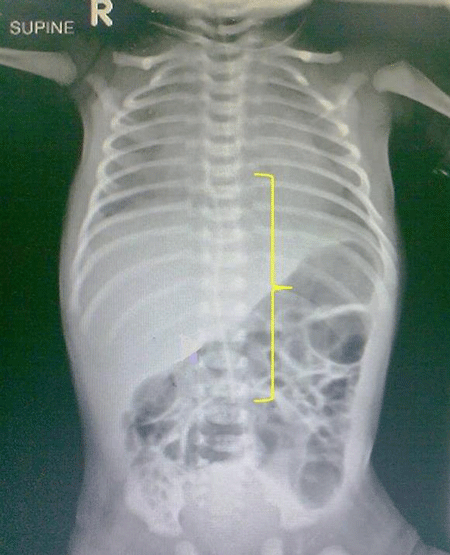

A 34-week male neonate weighing 1.8 kg was admitted in NICU for meconium aspiration syndrome. A 3.5 Fr UVC was used during initial days of his stay. Once the neonate was stable and UVC was no longer required it was planned for removal. On 4th day of his life removal was attempted but during catheter removal the UVC got divided by a scalpel at the skin level while removing the retaining suture. An attempt to retrieve the fractured portion of UVC was planned by a local exploration but the end had retracted into the lumen of the umbilical vein and it was not visible. A skiagram [Fig-1] showed the lower end of the UVC to lie near the base of the umbilicus.

Figure 1: Fractured segment of UVC in midline (along the parenthesis) with upper end just above diaphragm and lower end at level of L3 vertebral body. |